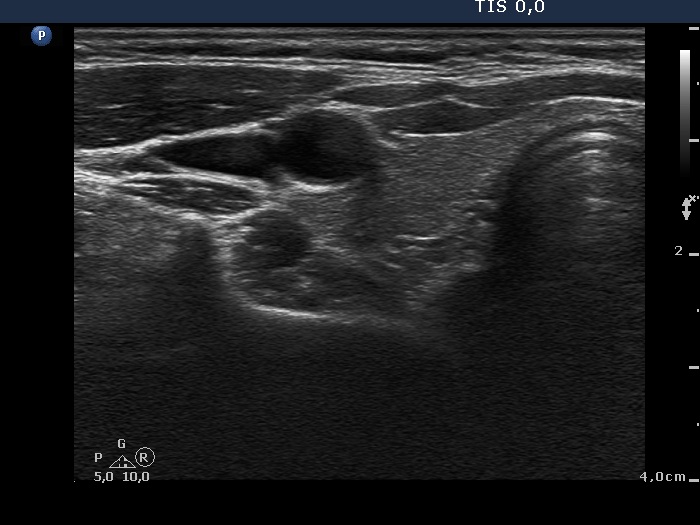

Clinical data: A 31-year-old woman was referred for evaluation of amenorrhoea. Otherwise, she had no complaints. She noticed a node in the right submandibular area for 5 years.

Palpation: There was an enlarged lymph node in the right submandibular area while there wasn't any abnormality in the thyroid.

Ultrasonography: The thyroid was intact. There was a reactive-type lymph node in the right submandibular area.